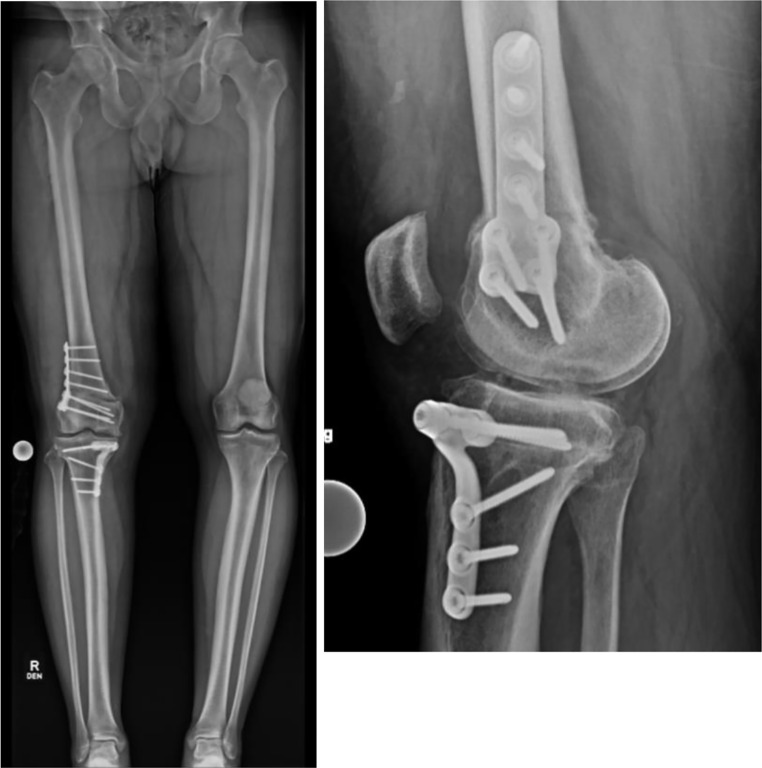

Purpose of review: Osteotomies around the knee are well-established techniques used to correct lower-extremity malalignment. While osteotomies of the proximal tibia and distal femur have traditionally been performed free-hand, the advent of Patient-Specific Instrumentation (PSI) in the form of custom 3D printed cutting guides and implants offers surgeons a greater ability to individualize surgical corrections to a patient's unique bony anatomy. This review aims to investigate the current state of the literature surrounding the use and outcomes of PSI for knee osteotomies and the benefits and drawbacks of PSI compared to traditional techniques.

Recent findings: Recent studies have demonstrated the potential benefits of PSI in knee osteotomy, including improvements in the accuracy of planned corrections, reductions in operative time and fluoroscopy exposure, and similar patient-reported outcomes. While increased costs and lead time represent drawbacks to the use of PSI, the technology continues to evolve such that these areas may improve over time. For osteotomy of the distal femur and proximal tibia, PSI offers surgeons an opportunity to improve surgical precision intra-operatively, with similar outcomes and complication rates as compared to traditional osteotomy techniques.